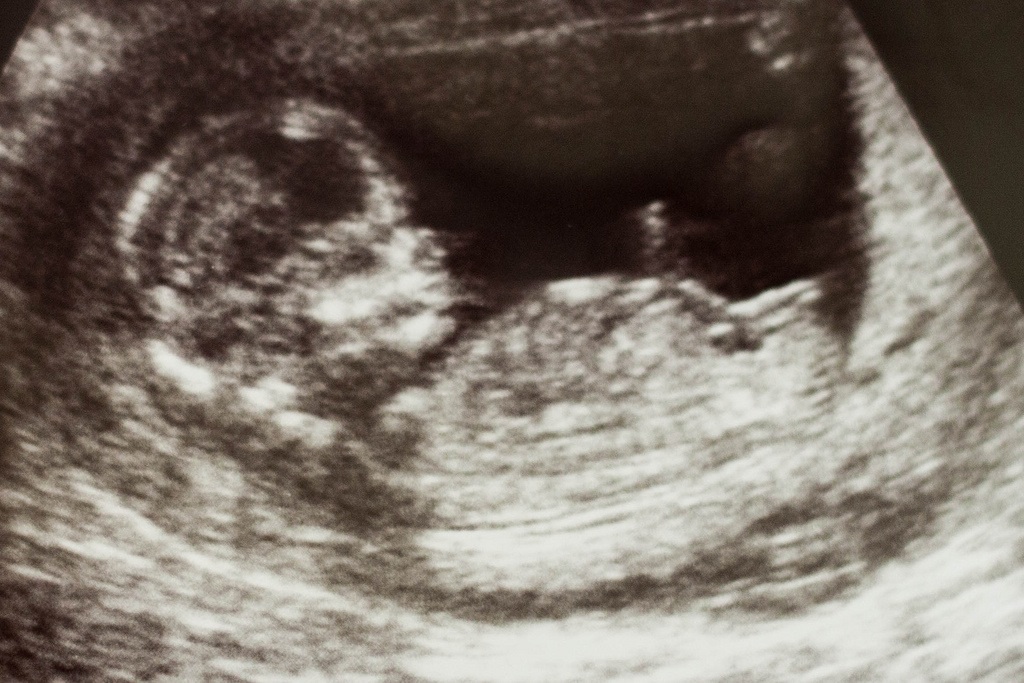

I'm driving myself crazy over here staring at this nub. What do you think, girl or boy?